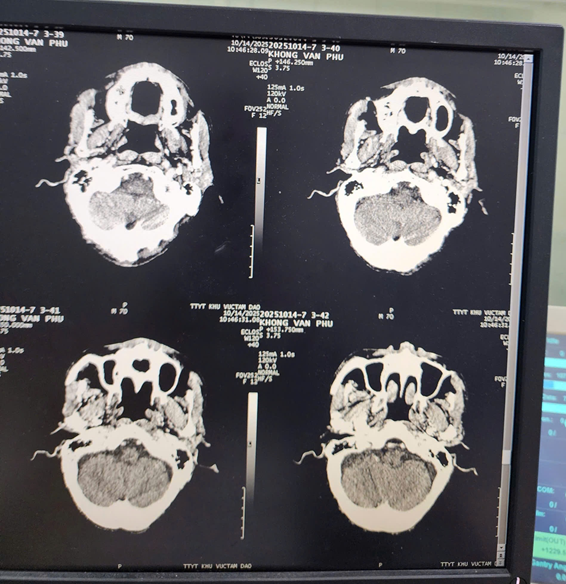

Chụp CT Scan là kỹ thuật sử dụng tia X kết hợp với máy tính hiện đại để tạo ra hình ảnh cắt lớp chi tiết, sắc nét, giúp quan sát rõ các cấu trúc bên trong cơ thể. Khi được tiêm thuốc cản quang, hình ảnh thu được càng rõ nét hơn, giúp làm nổi bật mô mềm, mạch máu và cơ quan nội tạng, từ đó hỗ trợ bác sĩ phát hiện và đánh giá chính xác các tổn thương. Kỹ thuật này cho phép hiển thị hình ảnh theo nhiều mặt cắt khác nhau như: ngang, dọc và đứng, giúp bác sĩ có cái nhìn toàn diện về vùng cần khảo sát.